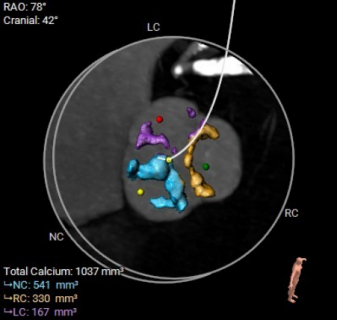

▲术前CT评估

团队没有贸然手术,而是先对庄爷爷进行了全面细致的术前评估:通过 CT 精准测量主动脉根部、冠脉高度、入路血管等关键数据,结合超声心动图评估心脏功能,最终确定为他实施 TAVR 微创手术。